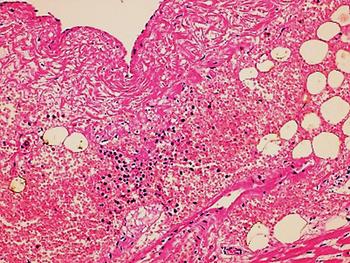

In the second case, the autopsy revealed jaundice, haemorrhages in temporal muscles, brain oedema, and multiple haemorrhages in epicardium; haemorrhagic myocarditis (Fig. 3); pericardial and pleural bilateral effusions; oedema and focal haemorrhages in both lungs; ascites, hepatic lesions characterised by portal triaditis; mild endothelial proliferation and perivascular mononuclear infiltrates in the lobes and splenomegaly. Microscopic examination of haemorrhagic lesions confirmed the presence of vasculitis.

Fig. 3. Micro haemorrhagia in the myocardium (HE 10×).